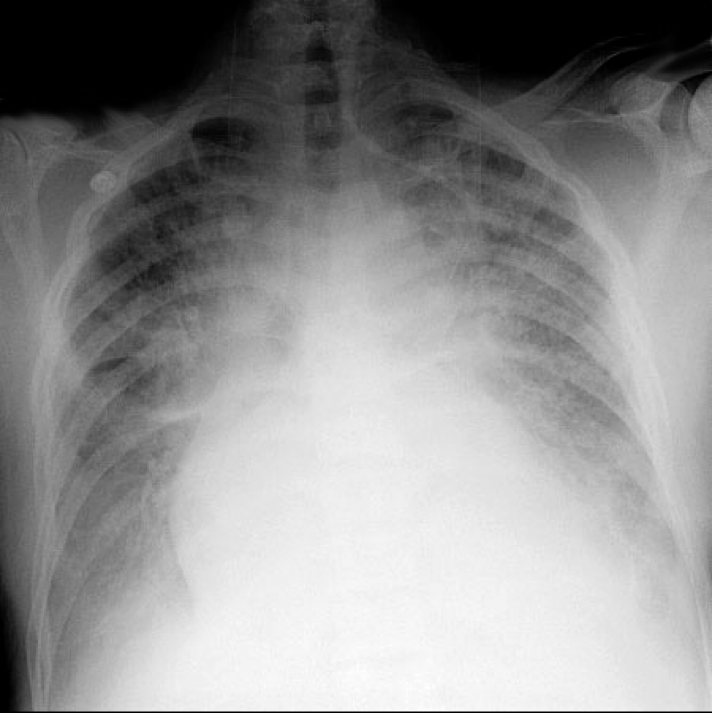

- Cardiomegaly (not in diastolic failure)

- Pulmonary edema

- Pleural effusion

- Kerly B lines (interstitial edema)

HOW TO CALCULATE CARDIOMEGALY ON CHEST X RAY

Horizontal diameter of the heart divided by the widest horizontal distance in the chest cavity.

If more than 0.5 → cardiomegaly (How to remember: heart/chest)